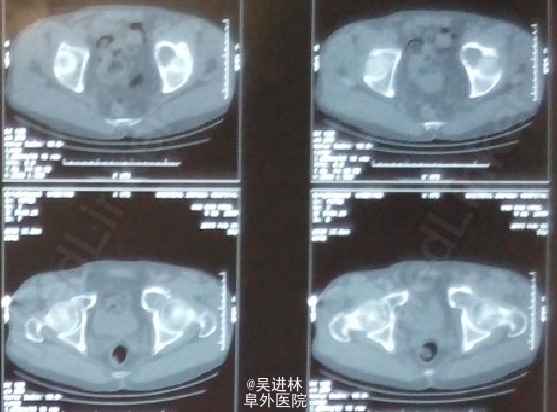

患者老年男性,主因“左髋部疼痛不适2年余”入院;查体:左侧腹股沟压痛+;活动度受限;4字试验+,托马斯征+;辅助检查:CT示左侧髋臼骨多发骨质破坏,累及周围软组织;全身骨显像示左髋臼窝核素浓聚灶;MIR描述如图。T-spot阳性!现在对于诊断基本持两种意见:因为患者病灶累及软组织,MRI上髂腰肌可见高信号,而且T-spot阳性,考虑TB。另外一种观点认为:病人除了T-spot并无其他TB征象,而且如果是TB的话,现在早就应该形成冷脓肿和窦道了,再者从MRI上来看,病灶呈膨胀性生长,边界清楚,所以考虑骨肿瘤可能性。what do you think?